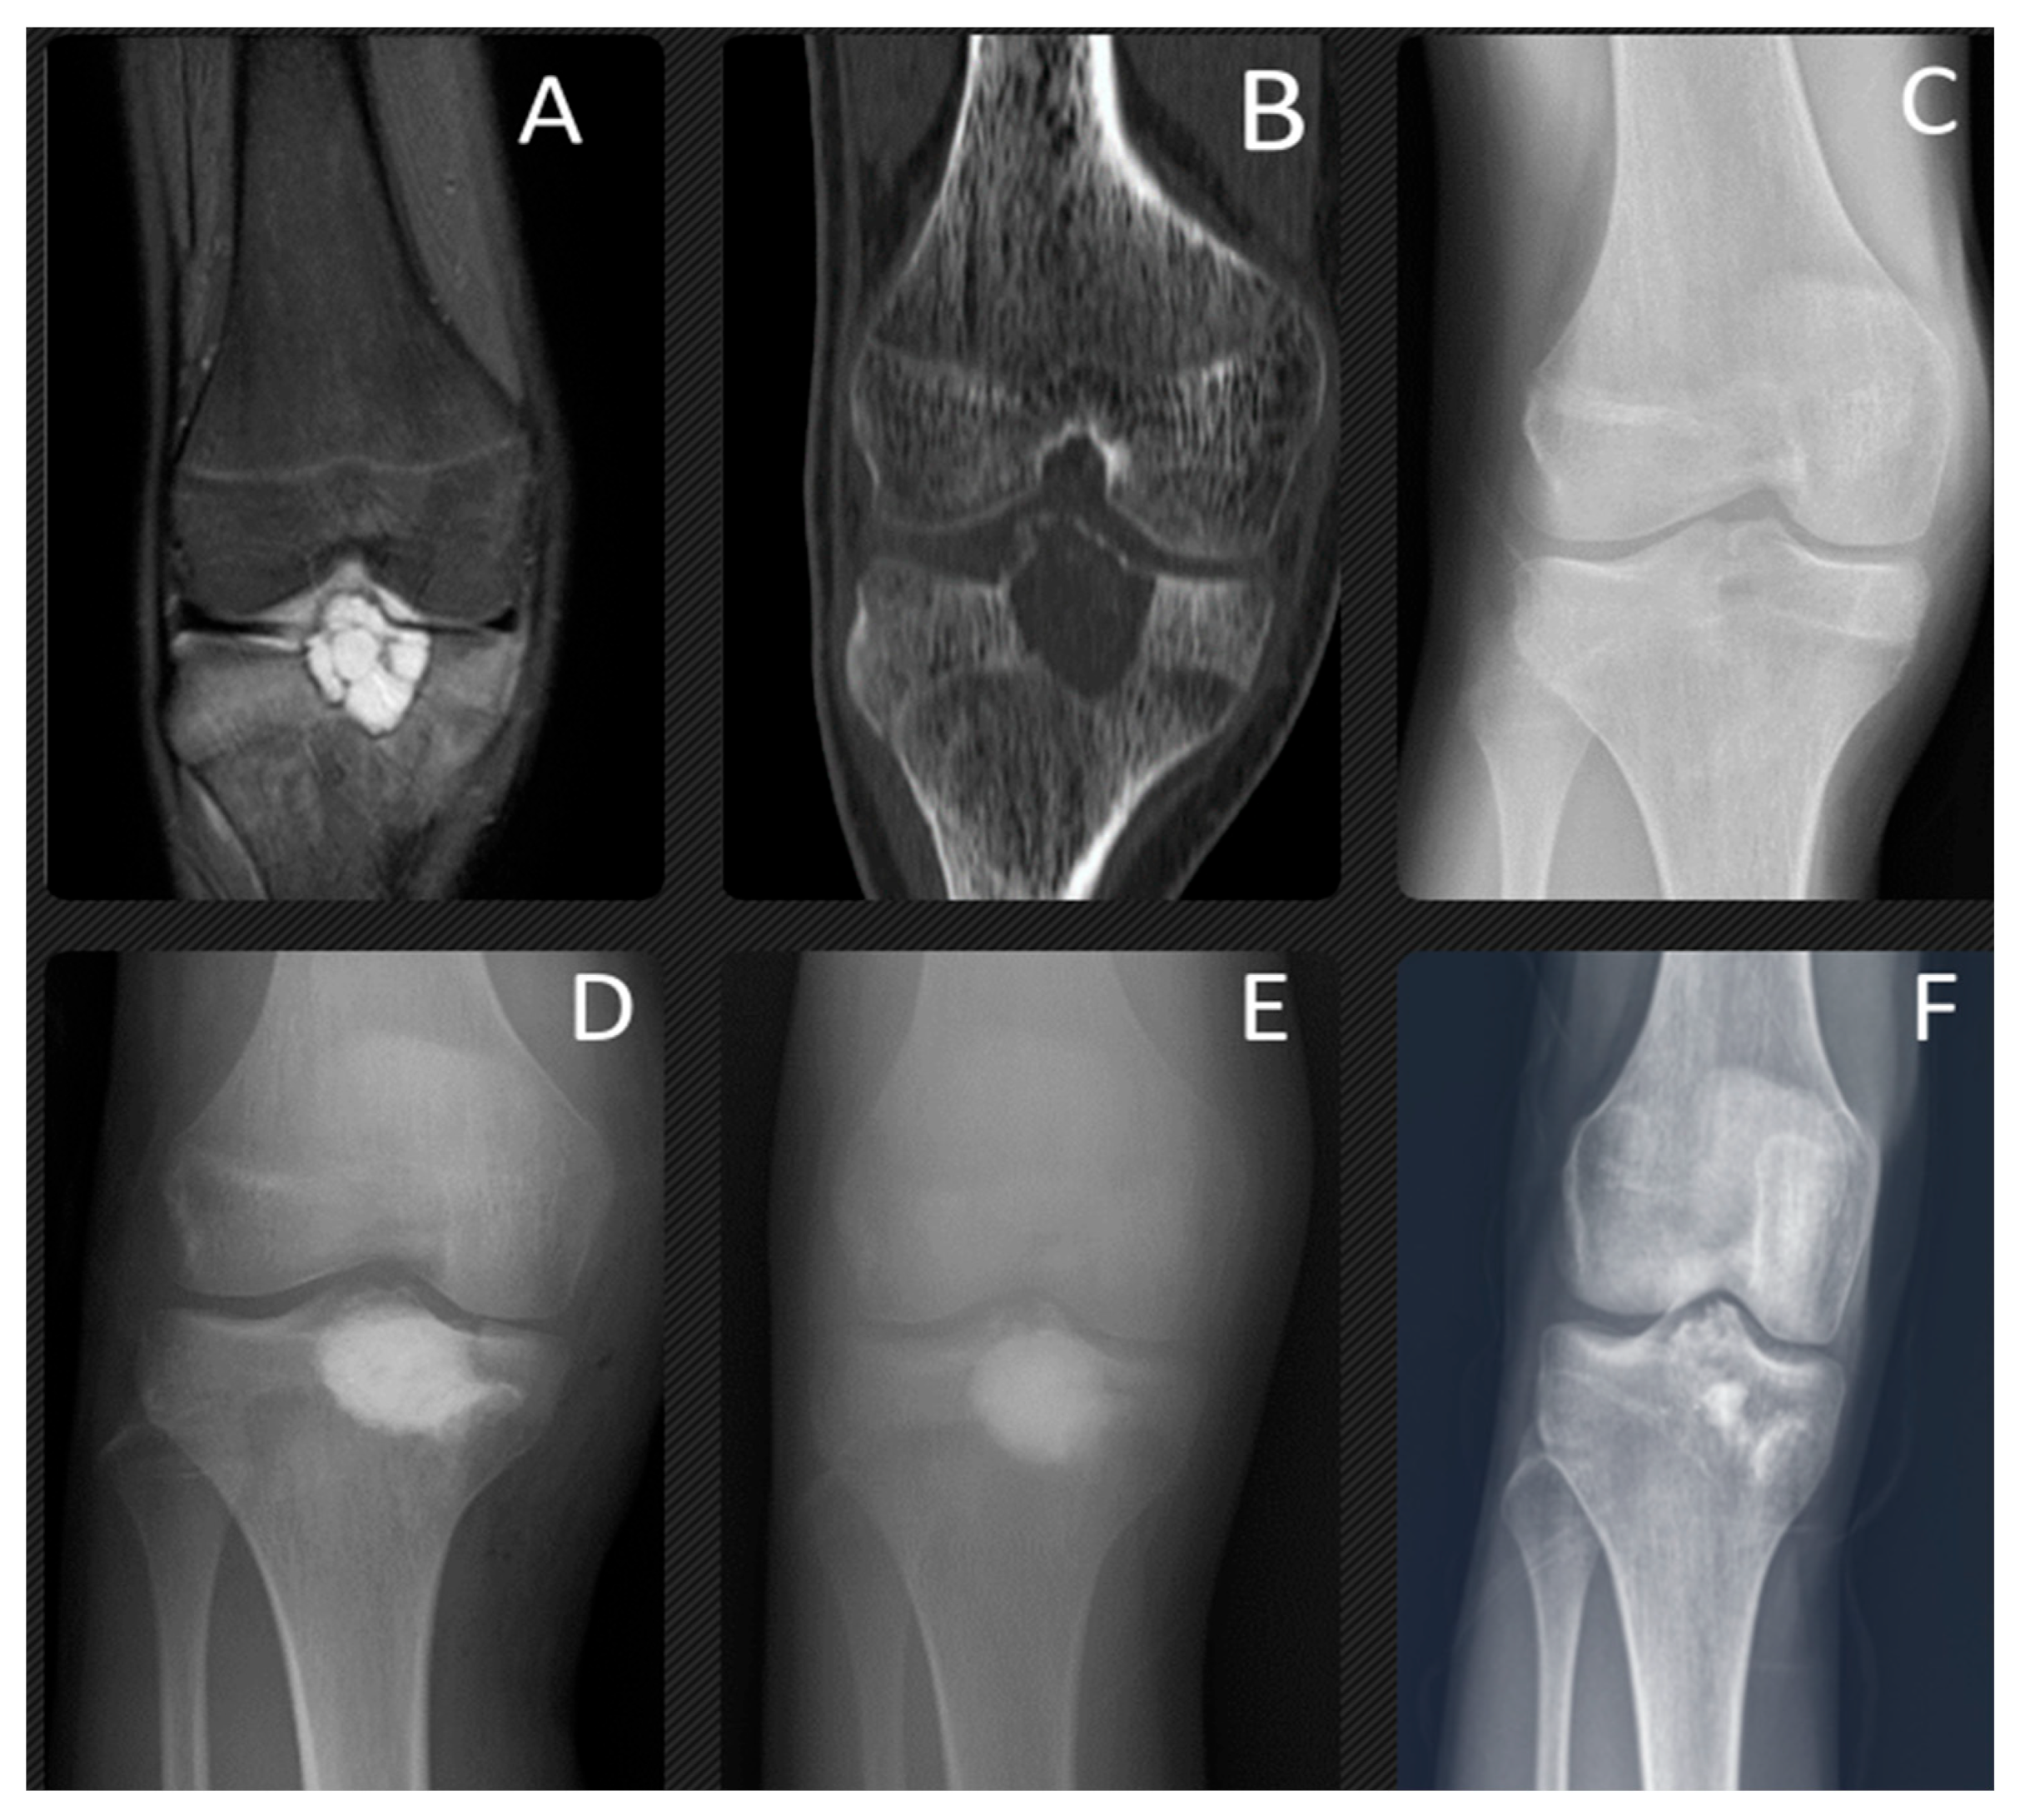

Figure 2. At the age of 14 years, this patient presented with chondroblastoma of the proximal tibia epiphysis, which is clearly shown on MRI (A), CT (B) and X-ray (C). The bone lesion was located in the proximal epiphysis of the tibia, with intralesional calcifications, an irregular sclerotic rim, and a thinned cortex. This active bone lesion crossed the physis. T2-weighted (A) coronal magnetic resonance images show the marrow edema of the epiphysis and metaphysis surrounding the chondroblastoma. This was treated with aggressive curettage and filled with synthetic bone graft. The final radiographs were taken 1 year (D), 3 years (E), and 7 years (F) after surgery. The anteroposterior (F) radiograph shows the lesion has completely healed and there does not appear to be any damage to the growth plate.